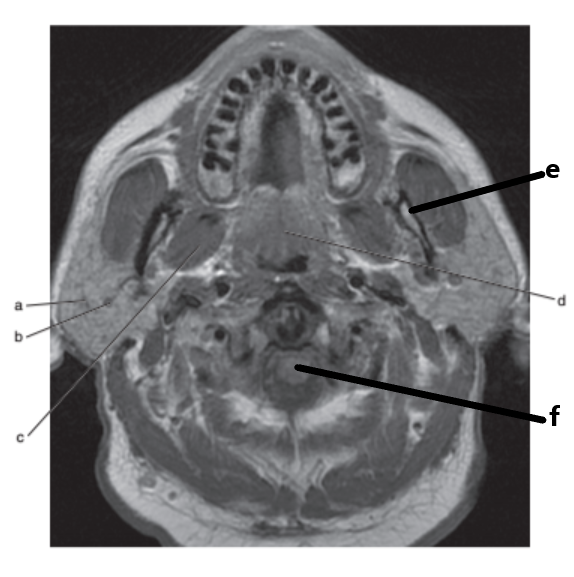

What anatomy is letter e ?

Nasopharynx

Parotid gland

Masseter muscle

Mandible

What is letter d ?

Soft palate